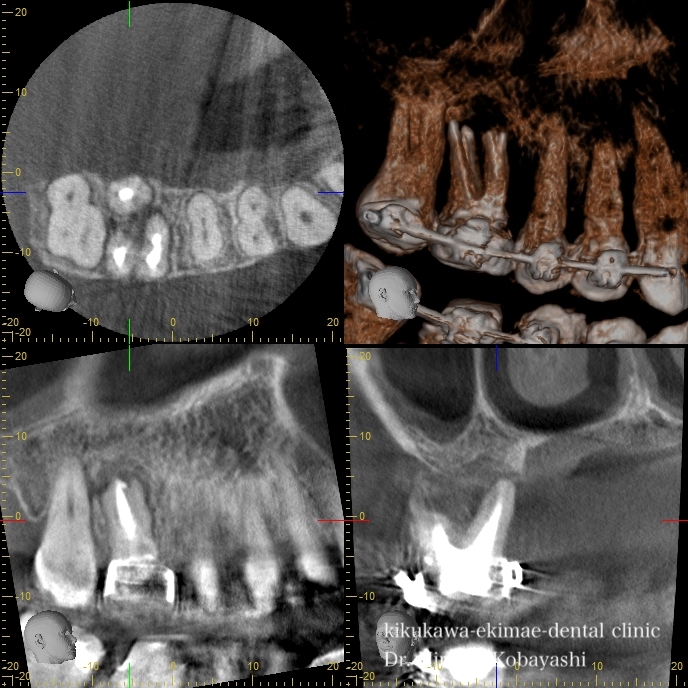

歯茎からオデキが出来たと来院されました。 CT撮影を行いますと、根の感染が見られました。感染の長期の放置により骨が溶けており、歯の保存が難しそうな状況でした。痛みもなく、特に生活に支障はありませんが、刻一刻と早期に歯を失う方向に進んでいます。おそらく、数年このままですと痛みもなくある日、ぐらぐらし、抜け落ちていたでしょう お話し合いの上、精密根管治療にて歯の保存を希望されましたので、治療を開始しました。   時間をかけ、顕微鏡を使用し感染の除去を行なっていきます。過去に根の処置を行なった時に入れたであろう薬剤や膿や出血が出てきます。 2時間程度のアポイントを3回お取りし、精密根管治療が完了しました。 オデキはなくなり、無事歯を残す事が出来ました。   CTにて経過を見ますと骨の再生が起きています 約6ヶ月〜程度かけて骨の再生が起こります。 リスク 極端に硬いものを噛むとかける可能性があります。 各種治療費はこちらから